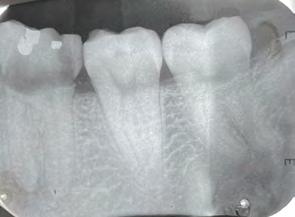

Paciente masculino de 29 años de edad, sin antecedentes médicos de interés acude al servicio de Cirugía Maxilofacial, el cual acude a la con sulta por odontalgía asociado al pri mer molar inferior izquierdo (Figura 1). Realizamos estudios radiográficos de dicho órgano (Figura 2), siendo valorado por especialista en prótesis y endodoncia quienes refieren no ser candidato para rehabilitación y tra tamiento de conductos con un pro nóstico poco favorable. Motivo por el cual se ofrece la opción de realizar TD del tercer molar inferior izquierdo al lecho quirúrgico del primer molar

Figura 2. Radiografía dentoalveolar inicial. Trasplante dental de terceros molares

Figura 3. Alveolos dental postextracción de primero y tercer molar inferior izquierdo. Figura 4. Punto de sutura en cruz para estabilidad de tercer molar inferior izquierdo y cierre del resto de las heridas. Figura 5. Radiografía dentoalveolar postoperatoria.